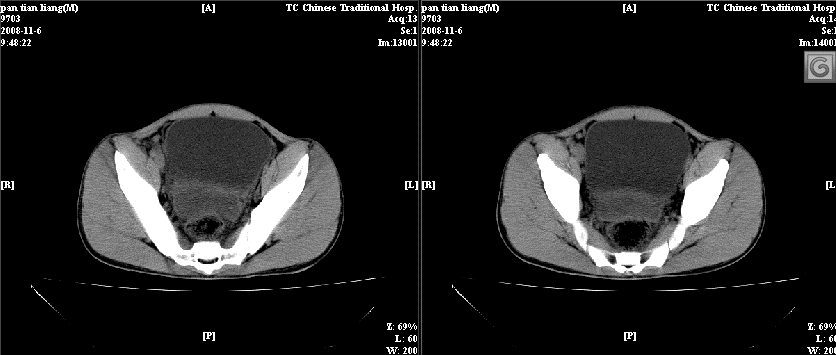

以下是引用dxm在2008-11-6 13:32:00的发言:[br]膀胱直肠窝积液 盲肠璧增厚 小肠淤积

以下是引用zsl6918在2008-11-6 14:13:00的发言:[br]如果阑尾炎病史明确,那腹腔及盆腔改变考虑脓肿形成.

以下是引用zjzjr在2008-11-6 14:37:00的发言:[br]支持阑尾炎伴盆腔及右髂窝脓肿形成